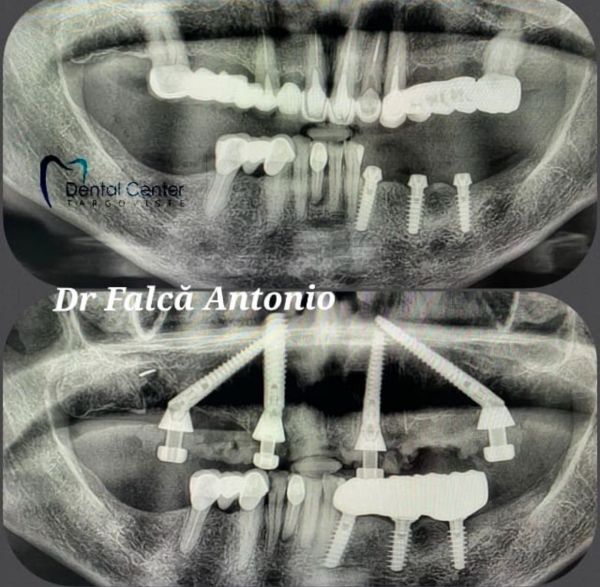

Targoviste Dental Center - servicii de inalta clasa in chirurgie dento-alveolara, stomatologie si RADIOLOGIE DENTARA DIGITALA

Targoviste Dental Center reprezinta o noutate in peisajul stomatologic dambovitean,evidentiindu-se prin calitatea serviciilor si profesionalismul excelent de care da dovada.

Clinica noastra este situata intr-un sediu ultramodern in zona 2 Brazi, strada Matei Basarab nr.38, dotat cu aparatura stomatologica de ultima generatie, computer tomograf dentar, sistem radiologic citeste tot

digital, echipamente de sterilizare cu rating maxim de siguranta si materiale stomatologice de cea mai buna calitate.

Dr. Antonio Falca